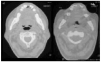

MI-E. Insufflation is forced inhalation of greater volumes than those the patient can achieve with his or her own inspiratory muscles. Exsufflation is forced expiration of greater volumes and at more rapid flow rates than those that can be obtained by the expiratory muscles. MI-E consists in providing the lungs with deep insufflation (at a pressure of 30-50 cm H2O) followed by immediate forced exsufflation (negative pressure of 30-50 cm H2O). With an inspiratory time of 2 seconds and an expiratory time of 3 seconds, there exists a very good correlation between the pressures used and the flows obtained.69 The combination of exsufflation with an abdominal or thoracic compression can increase expulsion flows68 (Figure 4). When manually assisted coughing is incapable of generating an effective PCF or when the patient is incapable of cooperating, MI-E is the most adequate option68 (Figure 5). MI-E applied with an oronasal mask can generate PCFs greater than 2.7 L/s in motor neuron disease patients, with the exception of those with very acute bulbar dysfunction,62 in whom there exists great instability of the upper airways.59 If, in normal subjects, the sudden application of negative pressure at this level produces reflex activation of the genioglossus to maintain permeability,70 in those patients with diminished strength and speed of the pharyngeal muscles71 there will be obstruction during the expiratory phase (Figure 6). Therapeutic intervention requires some 5 cycles, followed by a brief period of normal respiration (or return to the ventilator) to avoid hyperventilation. The technique should be repeated until secretions are expelled and desaturations caused by mucous plugs are corrected. During upper airway infections, exsufflations may be necessary every 10 minutes. When mucous plugs are eliminated in acute episodes in ventilated neuromuscular patients, MI-E may attain 300% improvement in VC as well as normalization of hemoglobin saturation.60 Counter indications of the technique include previous barotrauma, the existence of bullae, emphysema, or bronchial hyperreactivity. Secondary effects, such as pneumothorax, aspiration, or coughing up blood are reduced considerably by treating the aforementioned counter indications. On the other hand, gurgling noises and abdominal distension are rare and can be eliminated by lowering the insufflation pressure. The significant increase of forced expiratory flows in periods immediately following post-exsufflation indicates that MI-E does not provoke obstruction of the airways.60 As patients with spinal shock can present bradycardias, MI-E should be carried out with care in them, with gradual increase in pressures or premedication with anticholinergics. In patients with very low VC who have not previously received maximum insufflations, the use of high pressures may cause thoracic muscle discomfort; thus, progressive increase is also indicated. When patients have a PCF greater than 4.5 L/s, MI-E is not necessary since it will not increase cough flows.62

Fig. 6. Computerized axial tomography scans showing the difference inpermeability of the upper airways during an insufflation maneuver withthe Emerson Coflator and during exsufflation in a patient withamyotrophic lateral sclerosis and bulbar dysfunction.